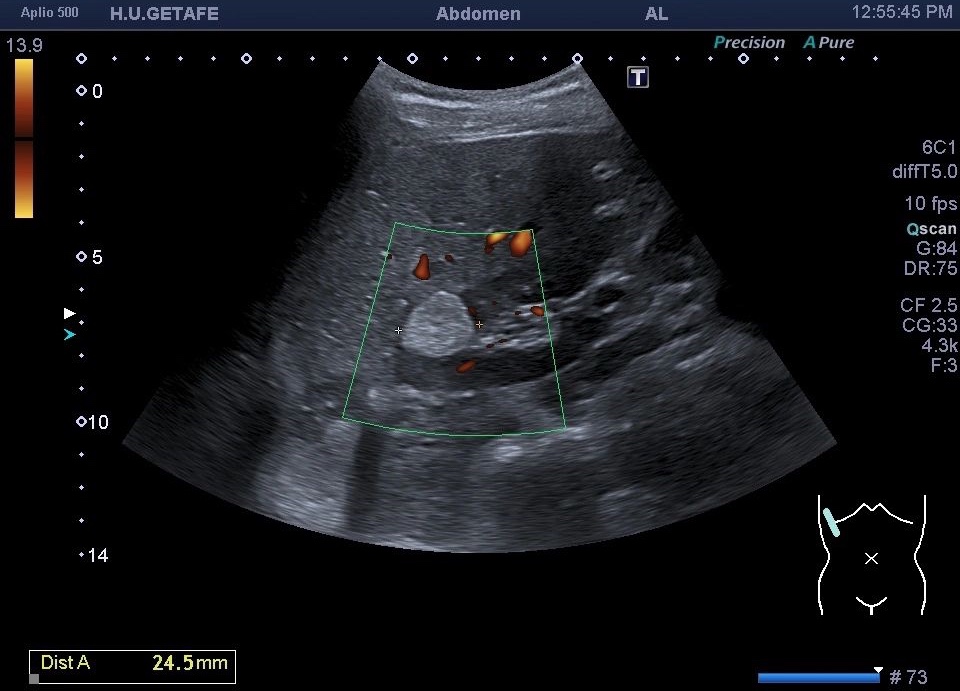

Deben demostrarse siempre en axial y sagital y usar Doppler color y Modo Angio.

1. hiperecogénicos

2. Isoecogénicos con la grasa

3. Homogéneo

4. Corticales

5. Sus bordes son bien definidos

6. Pueden ser lesiones exofíticas